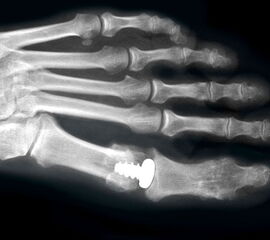

Resultate:

Die ersten Versuche mit der Prothetik am Großzehengrundgelenk wurden mit metallischen Hemi-Implantaten (Abb. 13, 14) vorgenommen. Eine Studie 47 mit größerem Kollektiv im Langzeitverlauf zeigte befriedigende Resultate, trotzdem hat sich die Technik bis heute nicht wirklich durchgesetzt. Der gleiche Autor verglich die Endoprothese mit der periartikulären Osteotomie und konnte keine wesentlichen Unterschiede feststellen 48. Eine neuere Studie vergleicht die Hemiarthroplastik mit der Arthrodese und der Resektionsarthroplastik und kann keine signifikanten Unterschiede feststellen 49. Metall–Polyäthylen-Paarungen zeigten eine hohe Lockerungsrate der Komponenten, weshalb sich diese Paarung ebenfalls nicht durchsetzte 505152. Am meisten Erfahrung besteht mit der Silikonprothese. Initial als Hemiprothese propagiert 46, wurde wegen mangelhaften Erfolgen 5354 die Totalprothese mit zwei Schäften eingeführt 55. Die Langzeitergebnisse sind widersprüchlich 55565758 so dass wegen der Verunsicherung dieses Model aktuell nicht regelmässig zum Einsatz kommt.